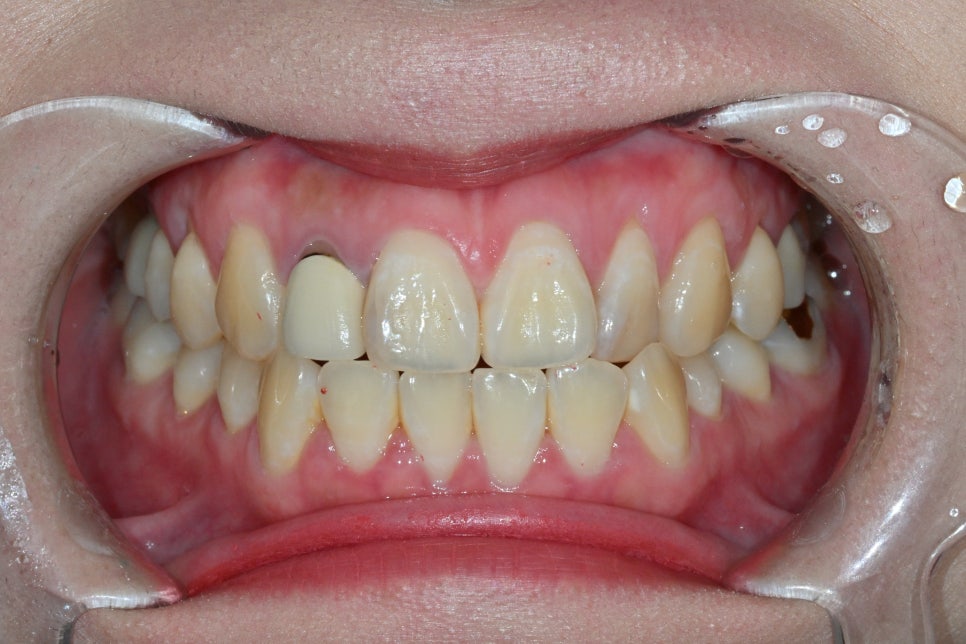

Changes after treatment

<BEFORE>

<AFTER>

Natural appearance of the gum line restored

A color harmony with the surrounding teeth

Improvement of the sense of incongruity in the front teeth

The response that it “looks like a natural tooth”

was especially impressive.